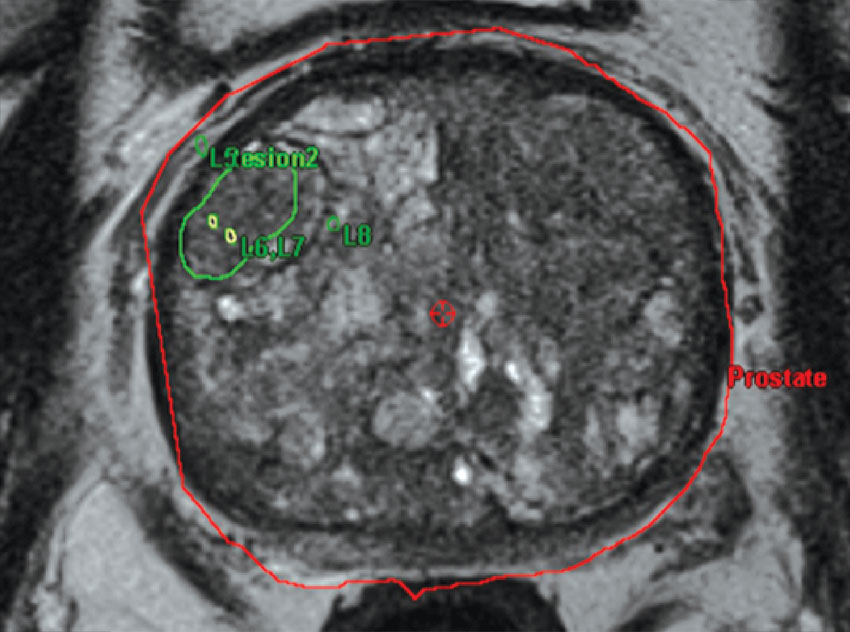

Πρόσφατα το Νοσοκομείο μας απέκτησε καινούργιο σύστημα που στηρίζεται σε σύντηξη εικόνων μαγνητικής τομογραφίας και πηγής υπερήχων (fusion) που επιτρέπει τη στοχευμένη βιοψία ύποπτων βλαβών στον προστάτη αδένα, καθώς ένα ποσοστό ύποπτων εστιών αυτού δύναται να εντοπισθούν μόνο στη μαγνητική τομογραφία (Πολυπαραμετρική Μαγνητική Τομογραφία).

Η μέθοδος υπερτερεί στην έγκαιρη διάγνωση του καρκίνου του προστάτη συγκριτικά με το προηγούμενο σύστημα βιοψιών. Μειώνει τον αριθμό των ψευδώς αρνητικών αποτελεσμάτων και των επαναλαμβανόμενων συνεδριών βιοψίας, και αυξάνει την αποτελεσματικότητα και την ευαισθησία της μεθόδου.